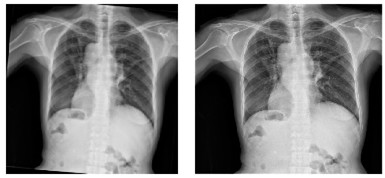

Table 2 shows the chest X-rays from three categories: pneumonia, tuberculosis and normal chest X-rays. The pneumonia image highlights red circles to indicate where the infection has occurred in the lungs. The image of tuberculosis reveals the usual signs, including abnormal conditions in the lungs. On a normal chest X-ray, the lungs are healthy and show no signs of abnormality. Many DL models in medical diagnostics were trained with these images.

Pneumonia Image | Tuberculosis Image | Normal Chest X-ray |

![]() | ![]() | ![]() |